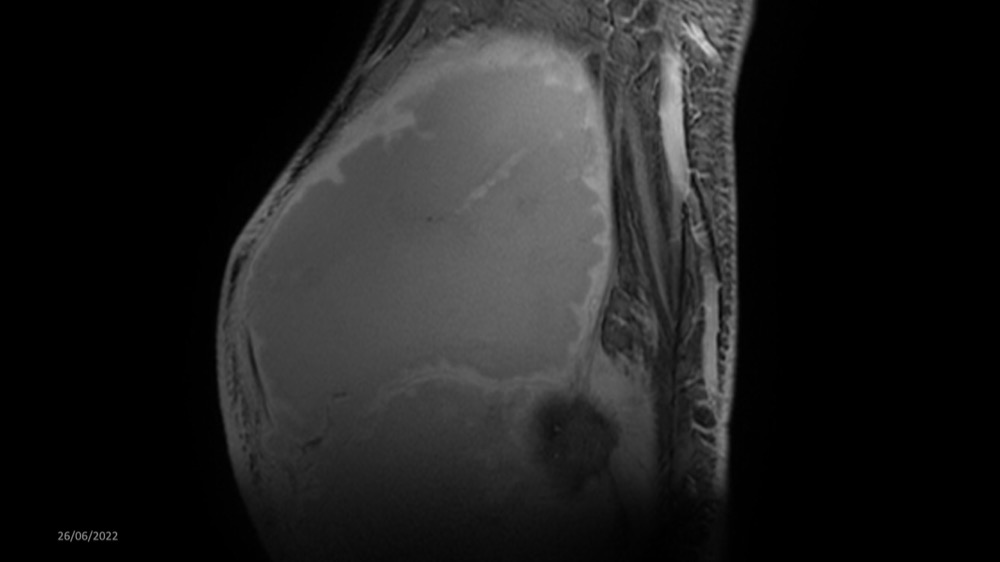

Reichert / Amar / Tordjman / Carlier 29/06/2022